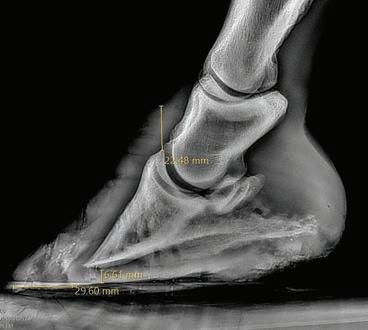

Notice how DSLD changes the conformation of the entire rear limb and causes hyperextension of the stifle, hock, and fetlock joints.

Photo: Courtesy Dr. Robert Koontz

Trimming and farriery

Correct hoof balance is crucial. Therapeutic trimming and appropriate shoes or boots may help relieve strain on the suspensory ligaments. Look for a farrier experienced in managing biomechanical disorders, who understands the importance of balancing both toe length and heel angle.

Why what’s under your horse matters

When a horse moves, every step transfers the loading force up the leg. The hoof is the first structure to hit the ground, and the way it is shaped, balanced, and maintained determines how that force travels through tendons, ligaments, and joints. Get it right and you’re protecting some of the most injury-prone tissues in the horse’s body. Get it wrong and you could be quietly adding strain to structures like the deep digital flexor tendon and the suspensory ligament until one day they fail. How does hoof balance change tendon and ligament strain?

Excess toe length

When the toe grows too far forward, the hoof takes longer to roll forward and leave the ground. This stage is known as breakover, and when it is delayed the tendons and ligaments work harder with every step. This forces the deep digital flexor tendon and suspensory ligament to work harder to lift the limb. Over time this adds fatigue and increases injury risk.

Low or collapsed heels

When the heels are too low and the back of the foot lacks strength in the digital cushion and collateral cartilages, the hoof sinks more with each step. This puts extra stretch and strain on the tendons and the structures that support the fetlock. The right amount of heel support, when needed, can help take the pressure off tendons and ligaments.

The suspensory ligament’s main function is to support the fetlock and stop it from overloading and dropping too far toward the ground when the horse is in motion. Any hoof shape or landing pattern that increases fetlock extension such as long toes, underrun heels, or negative palmar angles pushes more load into this structure. In horses recovering from a suspensory injury, correcting hoof mechanics is essential. Without it, rehabilitation stalls or reinjury is almost inevitable.

What therapeutic trimming really means

Therapeutic trimming is a deliberate approach to restoring correct hoof pastern alignment, shortening the toe lever, bringing breakover back under the centre of rotation, and building a strong supportive heel base and frog for a heel first landing. It also addresses side-to-side imbalances so both branches of the suspensory share the load evenly. Changes are maintained with shorter trim or shoe cycles, often every four weeks. Each time your hoof care professional visits, their goal is to keep the hoof in correct form and function (or be constantly working towards this in rehab cases). This is why engaging a qualified professional who can work on a consistent, short cycle is such an important part of whole horse health. Therapeutic hoof care may involve shoes or composite materials, boots and pads, or leaving the horse barefoot. The method matters less than achieving the right mechanics, choosing what is best for your horse, and matching it to your ability to maintain the hooves between professional visits. Why the right hoof care professional matters